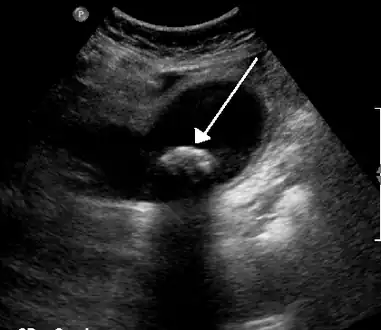

On abdominal ultrasound, sinking gallstones usually have posterior acoustic shadowing. In floating gallstones, reverberation echoes (or comet-tail artifact) is seen instead in a clinical condition called adenomyomatosis. Another sign is wall-echo-shadow (WES) triad (or double-arc shadow) which is also characteristic of gallstones.[37]

A 1.9 cm gallstone impacted in the neck of the gallbladder and leading to cholecystitis as seen on ultrasound. There is 4 mm gall bladder wall thickening.